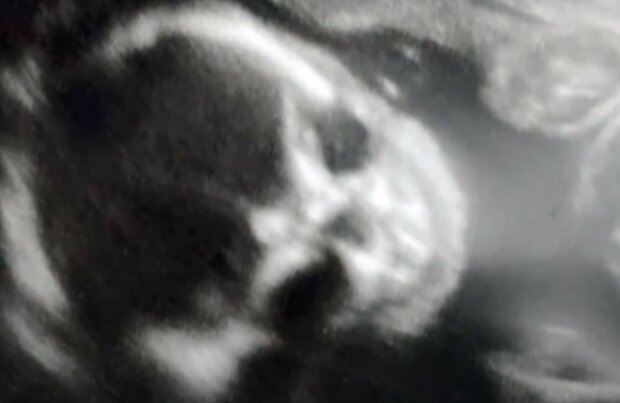

Niemowlęta nigdy nie wyglądają idealnie na mało czytelnymzdjęciu ultrasonograficznym, ale ta mama z Oklahomy miała szokującą niespodziankę, gdy obraz na jej pierwszym skanie wydawał się przedstawiać szkielet.

23-letnia Jessica Woods z Guthrie powiedziała, że ​​była trochę zdenerwowana, kiedy była w ciąży z Silasem. „Po pierwsze, wyglądało to jak normalne USG i wyglądał jak normalne dziecko” - powiedział Woods InsideEdition.com. „Odwrócił głowę i wtedy zaczął wyglądać jak szkielet. Byłam trochę przerażona”.

Była w ciąży z drugim dzieckiem w czasie badania USG, ale nigdy nie przypuszczała, że ​​pierwsze zdjęcie jej dziecka będzie wyglądać tak dziwacznie. Jak przyznała, żadno ze zdjęć ultrasonograficznych jej córeczki, starszej siostry Silasa, nie wyglądało w żaden sposób dziwnie, czy przerażająco.

W pierwszej chwili zastanawiała się, czy to normalne, czy wszystko jest dobrze z jej maleńkim synkiem, lecz gdy zapytała o to lekarza, który wykonywał jej wówczas badanie, usłyszała słowa niosące ulgę. Specjalista wyjaśnił jej, że synek wygląda normalnie i urodzi się zdrowy, a z obrazem ultrasonograficznym często tak bywa, że nie obejmuje wszystkich wymiarów i parametrów, przez co obraz często może przerazić.

Na szczęście reszta jej ciąży przebiegła spokojnie, a mały Silas przyszedł na świat jako zdrowy i szczęśliwy chłopiec mimo, że jego osobowość jest „zdecydowanie szalona”, jak to określiła jego szczęśliwa mama.